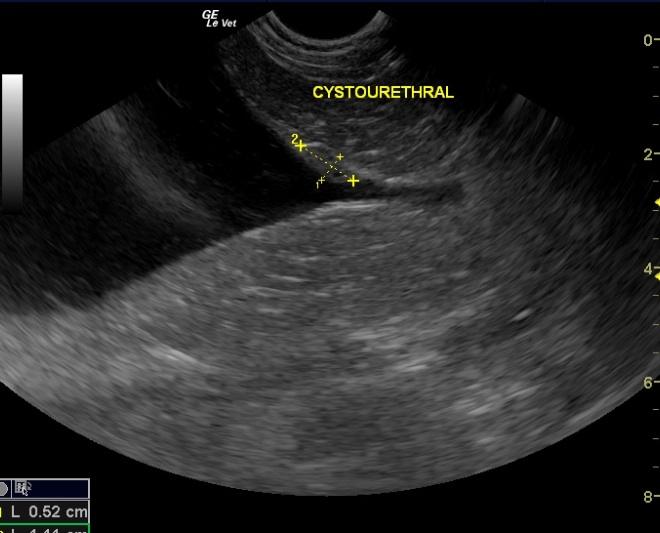

An 11-year-old FS Vizsla was presented for diarrhea, tenesmus, and stranguria for a few months. Rectal exam revealed minor thickening in the urethral region. A Canine diarrhea panel was positive for Clostridium Perfringens Enterotoxin A.